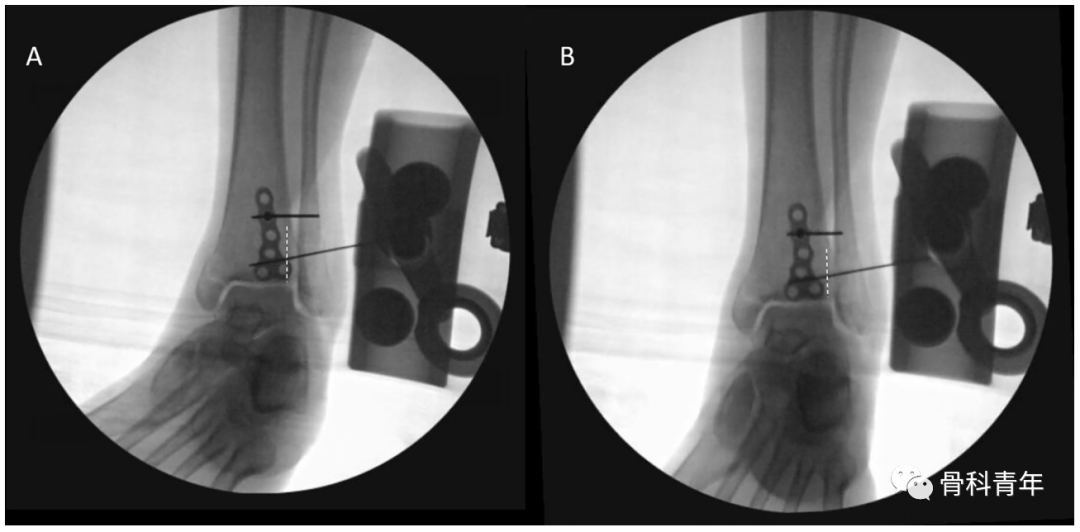

依上述研究结果,在如下的后踝钢板固定中,透视钢板部分位于PVSL线外侧,有影响下胫腓风险,因此将钢板内移至PVSL线内

图中白色虚线即为PVSL线。